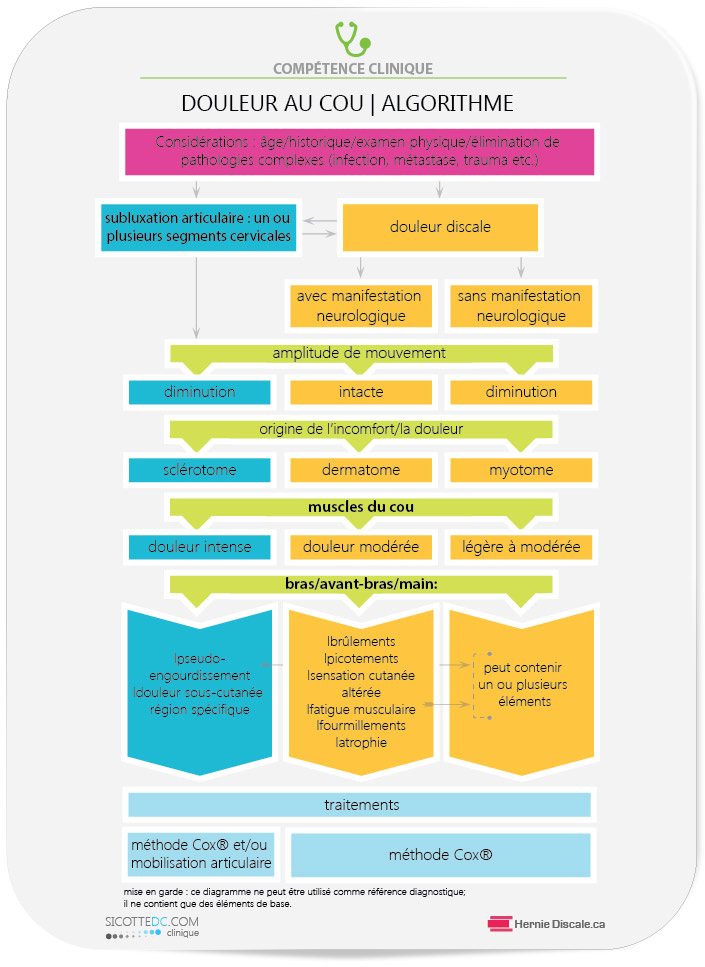

TRAITEMENT

Lorsque le patient entre en clinique avec une douleur aiguë à la colonne cervicale, le clinicien se doit d’explorer et d’éliminer toutes les possibilités autres que la subluxation articulaire. Au moment où le clinicien a la certitude que l’état est bénin, il peut procéder selon l’algorithme ci-contre.